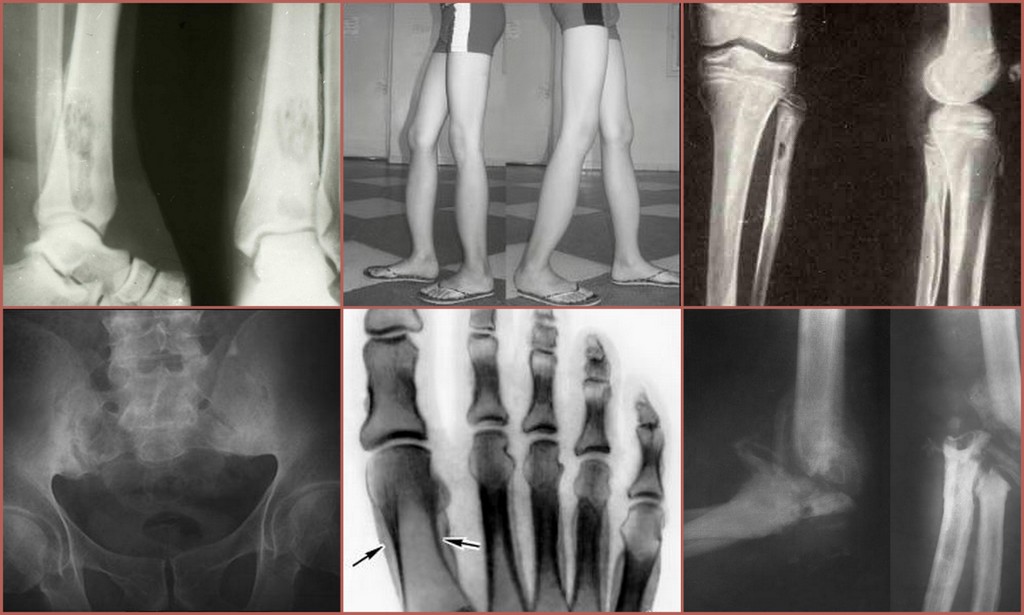

Рентгеновские снимки остеосклероза костной ткани